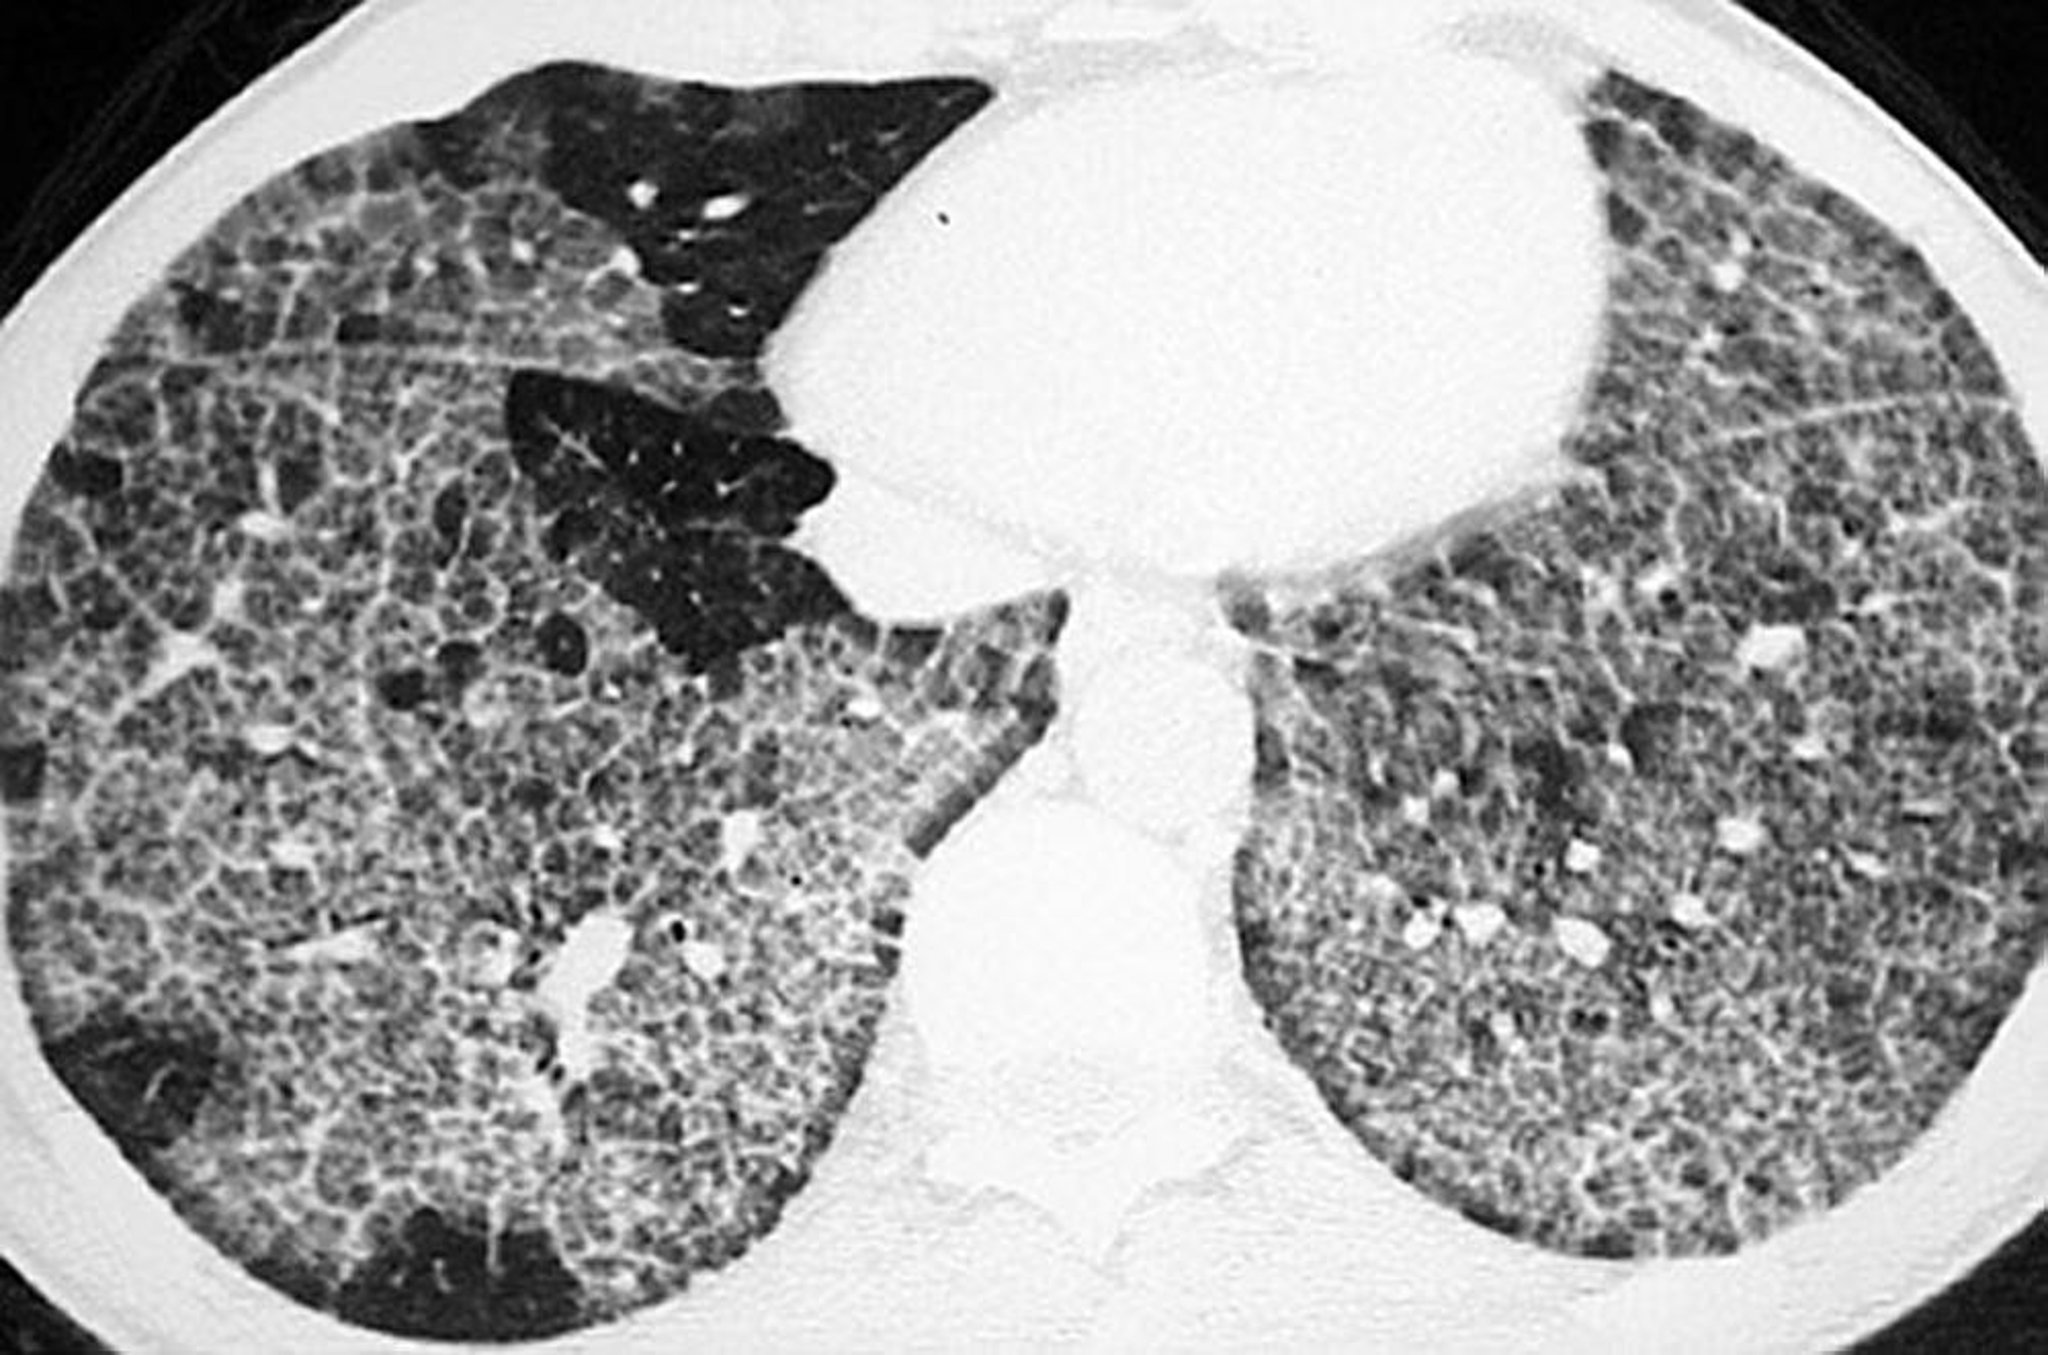

Protéinose alvéolaire pulmonaire (TDM)

La TDM à haute résolution montre une opacification en verre dépoli et des structures intralobulaires et des septa épaissies de formes polygonales ("crazy-paving").

Image courtoisie de Talmadge E. King, MD.